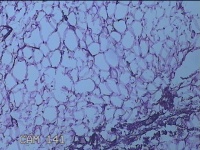

外阴部包块

性别

女

年龄

37岁

临床诊断

皮脂腺囊肿

一般病史

外阴部起包块一月余。

标本名称

大体所见

灰白暗红色包块2.3x1.8x0.8cm一个,表面糜烂,切开包块呈实性,切面灰白淡黄色,质软。

有那么点像脂肪瘤。